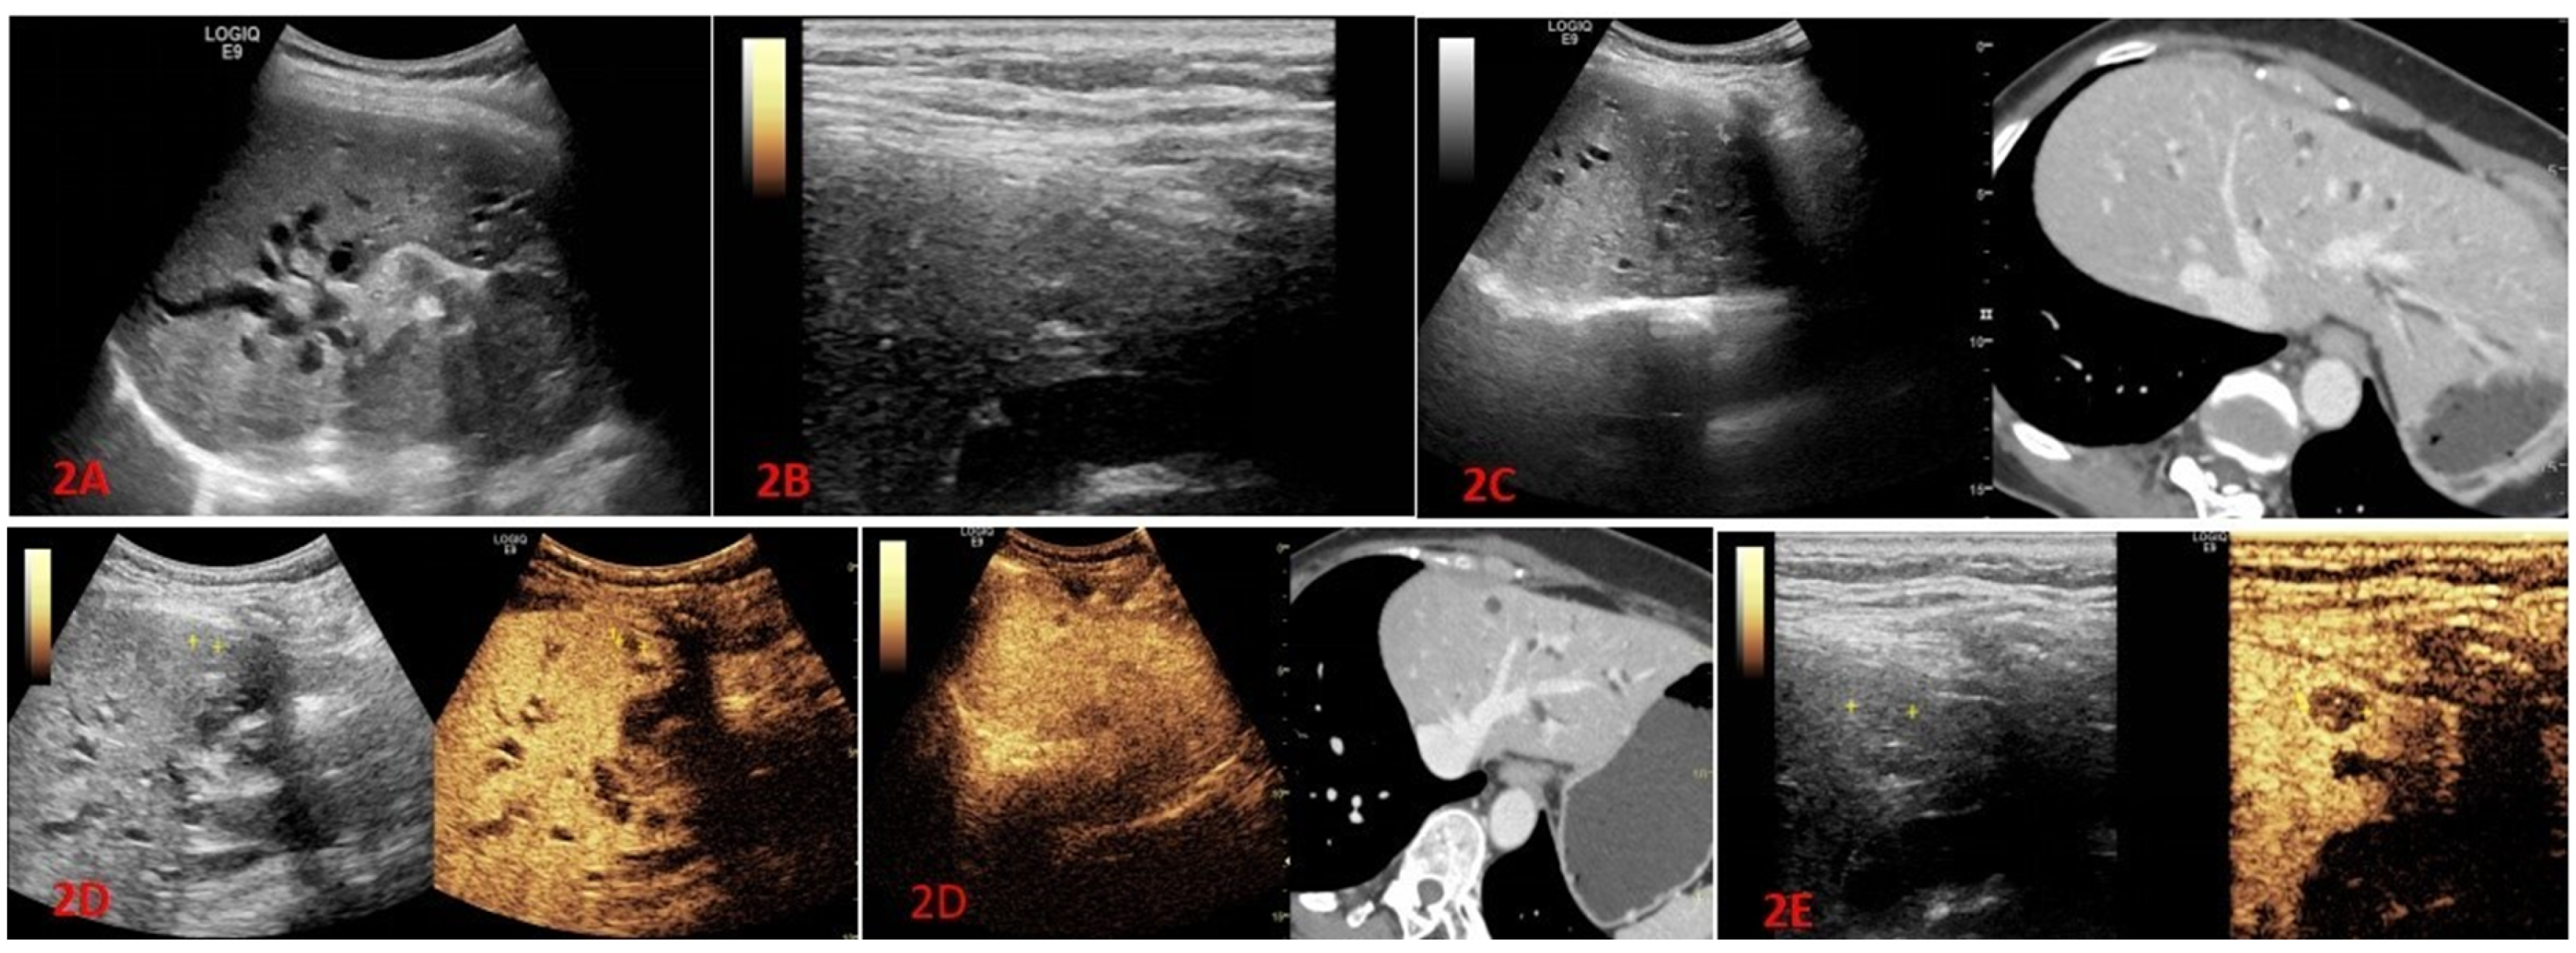

2.2.1. Conventional Ultrasound and Fusion Imaging Methods

2.2.2. High-Frequency Ultrasound Examination

2.2.3. Contrast-Enhanced Ultrasound Examination

2.2.4. High-Frequency Contrast-Enhanced Ultrasound Examination